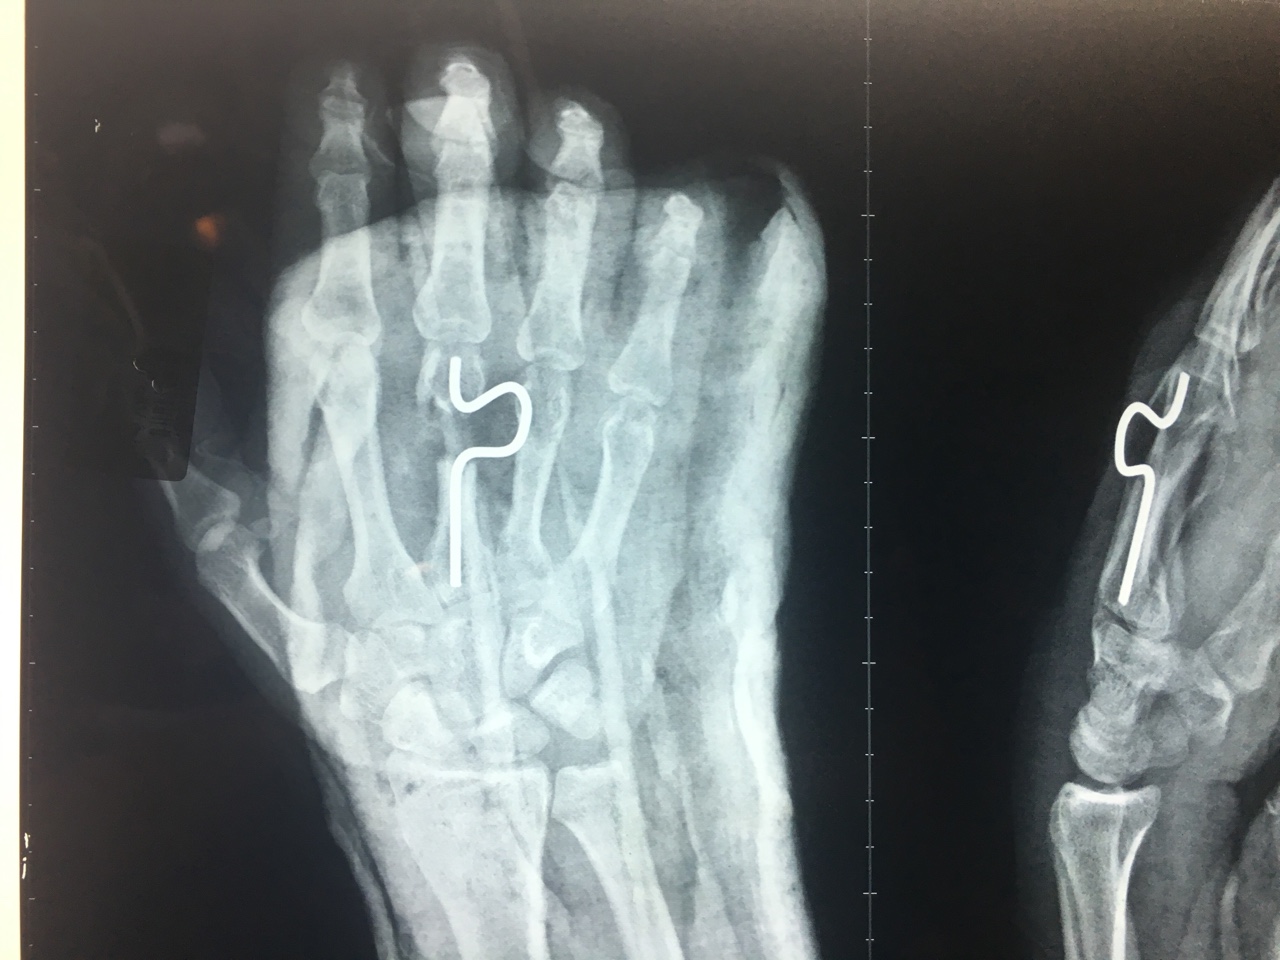

Mất da cuống bẹn